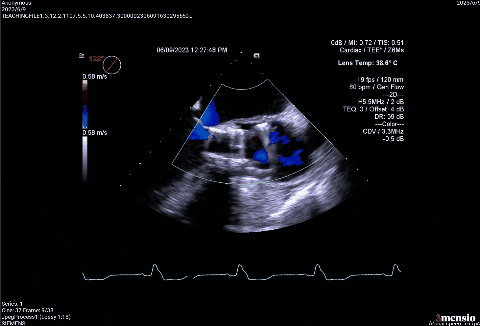

超声影像

血流动力学改善,瓣膜形态良好。